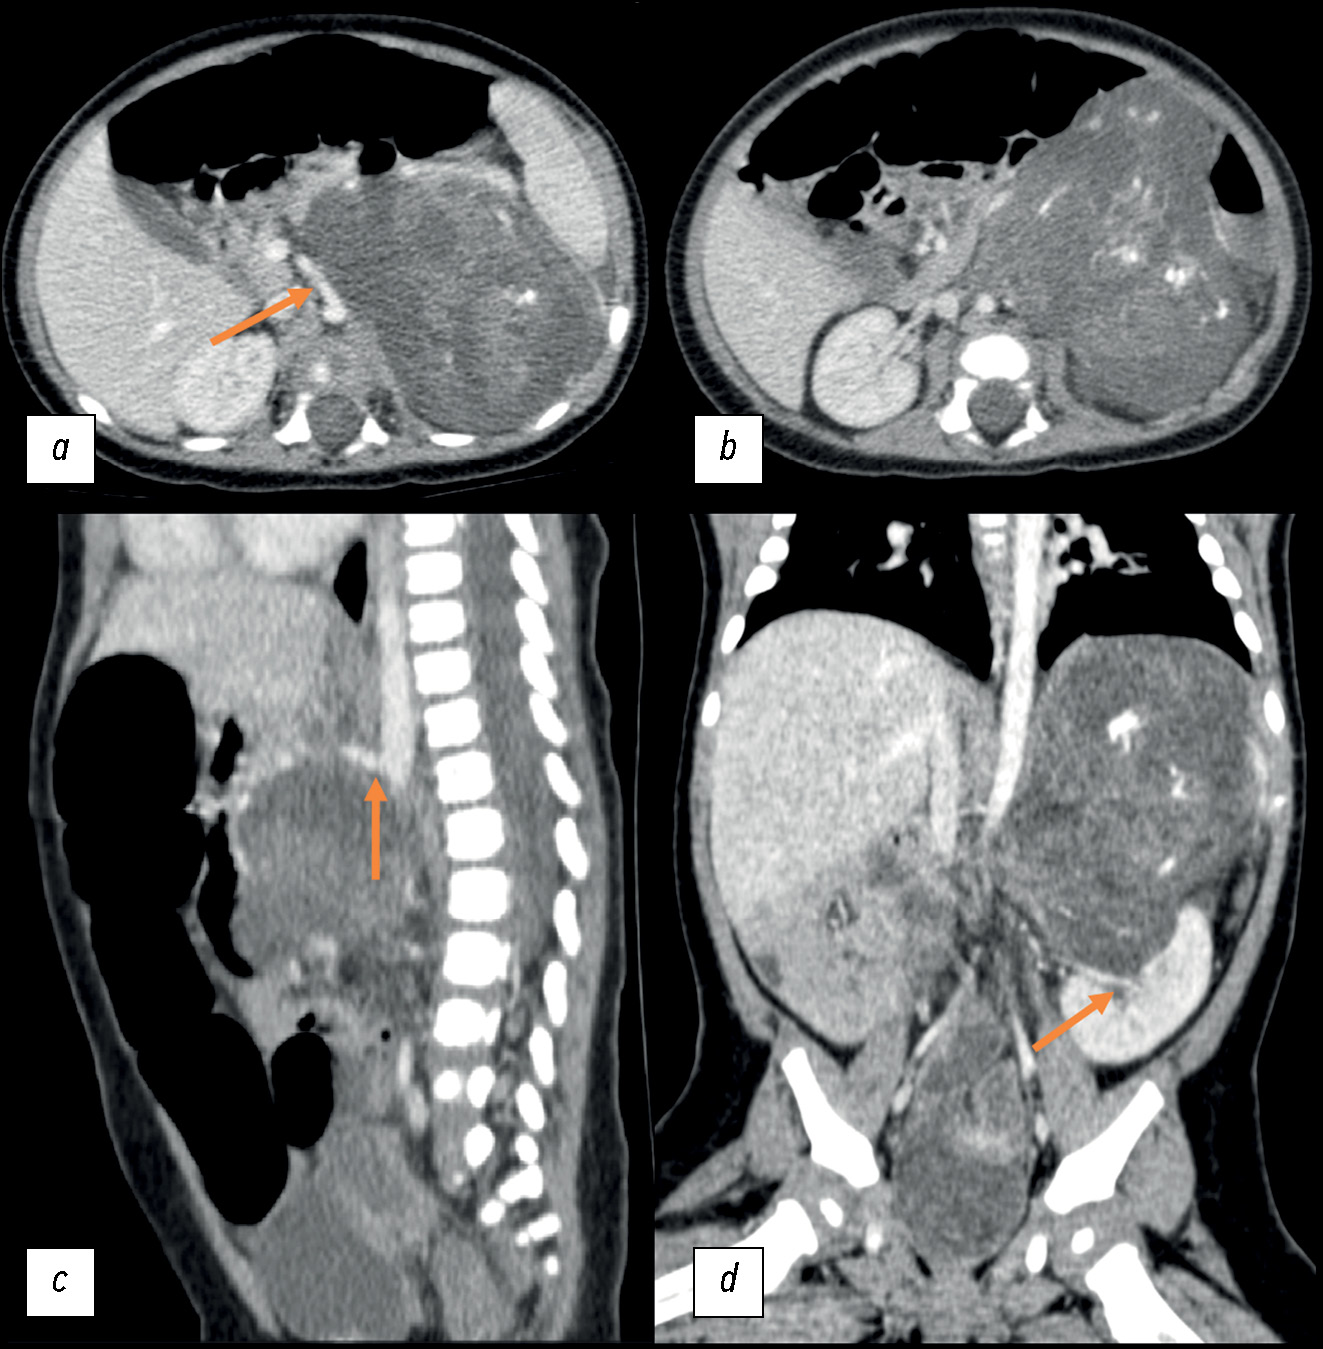

Множественные билиарные микрогамартомы, случайно диагностированные у пожилого пациента

Множественные билиарные гамартомы, также называемые комплексами фон Мейенбурга — это доброкачественные новообразования печени, которые могут быть выявлены случайно. Их нелегко обнаружить, если ранее не доводилось с ними встречаться, а также если соответствующие методы визуализации на момент обследования недоступны. К тому же их сложно отличить от других поражений печени на основании визуализационных данных. Таким образом, описание данного клинического случая направлено на пополнение библиотеки цифровых изображений, что позволит радиологу быстро и точно провести дифференциальную диагностику. Кроме того, подчёркивается важность тщательной рентгенологической оценки этого заболевания и необходимость мультидисциплинарного подхода с участием радиологов, гепатологов и патологов для постановки точного диагноза.

Пациент поступил в больницу для проведения компьютерной томографии и магнитно-резонансной томографии брюшной полости по рекомендации терапевта для оценки состояния билиарного дерева (магнитно-резонансная холангиопанкреатография) в связи с постоянными болями в животе. Пациенту никогда ранее не проводили инструментальное обследование брюшной полости, поэтому новообразования печени оказались случайной и неожиданной находкой.

Магнитно-резонансная томография выявила множественные доброкачественные образования в обеих печёночных долях, сопоставимые с комплексами фон Мейенбурга. Эти поражения представляют собой множественные гамартомы и ведут себя по-разному во всех последовательностях сканирования.

В ходе исследования были тщательно изучены изображения, полученные с помощью различных последовательностей магнитно-резонансной томографии. В печени обнаружены множественные очаги поражения с признаками доброкачественности, которые соответствовали диагнозу «множественные билиарные гамартомы».

Практикующие специалисты должны уметь распознать это заболевание и учитывать его при дифференциальной диагностике у пациентов с патологиями печени. Это позволит предотвратить ненужные вмешательства и выбрать правильную тактику ведения пациентов.